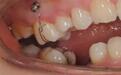

而随着支抗钉的出现呢,大大方便了医生的加力,基本上牙齿的移动可以达到随心所欲的境界,想让牙齿移动,支抗钉都可以解决这个问题,支抗钉是在骨质上旋进去一颗迷你型号的钉子,一般尺寸在1.0+mm,痛苦程度小,但是就这一颗小小的钉子,可以作为施力的单位,钉子在骨质里面是没有动度的,通过在钉子上挂个橡皮圈或者螺旋拉簧,就可以对牙齿施加移动的力量。

我们在改变牙齿前突,尤其是伴有面型前突的患者,拔牙的间隙,一般是想通过前牙的最大内收,来把缝隙关闭的,从而改变面型,不希望后牙前移来占据拔牙间隙,这种情况支抗钉就发挥很大的作用了,从支抗钉上挂一个橡皮圈,来牵引前牙内收。